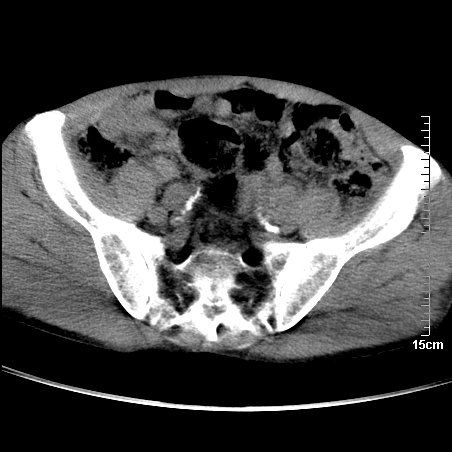

标题: CT16886:骶尾部占位:1.脊索瘤?2.巨细胞瘤?

平扫:

部分骶尾骨已被软组织密度的肿瘤所取代,同意“首先考虑脊索瘤,不除外转移瘤”的意见。

1、骶尾部巨大软组织肿块,部分骶尾骨以被软组织肿块代替,呈不规则侵蚀;病变突向盆腔内;增强扫描病变呈不均质强化;首先考虑脊索瘤。不支持的一点就是病变内无钙化。